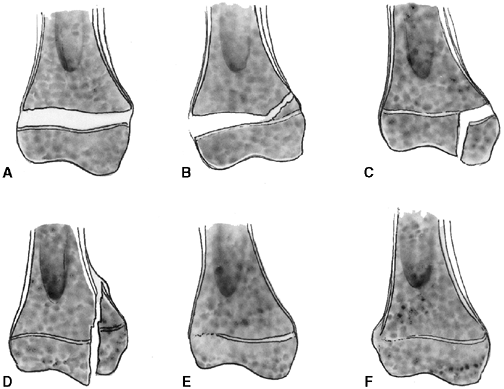

Several classification systems have been proposed since Foucher first

described different types of physeal fractures in 1863 (30). The most widely used classification of physeal fractures is that described by Salter and Harris (31). There are five types of fractures in this classification. Rang has added a sixth that is commonly recognized (Fig. 33.2) (32).

entire growth plate without evidence of a metaphyseal fragment. This

type of fracture is most commonly seen in infants and young children.

The epiphyseal fragment may be nondisplaced or minimally displaced,

making diagnosis difficult. Localized swelling and point tenderness may

confirm the diagnosis. The prognosis for resumption of growth is

excellent with a few notable exceptions, such as physeal separation of

the proximal or distal femur. Partial growth arrest may occur with more

severe trauma, or when periosteum is entrapped in the physis (33,34).

fractures. The fracture line passes through a portion of the growth

plate and exits through a triangular segment of the metaphysis that

remains attached to the intact portion of the growth plate. The

metaphyseal fragment (Thurston Holland fragment) is on the compression

side of the fracture. The prognosis for resumption of growth is

generally excellent, but the risk of growth disturbance varies with the

location of the fracture. Type II fractures of the distal radius rarely

lead to physeal closure (35), but type II fractures of the distal femur cause growth disturbance in approximately 50% of patients (36).

Figure 33.2 Salter-Harris classification. A: Type I is a transepiphyseal separation without evidence of a metaphyseal fragment. B:

In type II, the fracture line is through the physis, exiting into the metaphysis, leaving a small triangular portion attached to the physeal plate (i.e., Thurston Holland fragment). C: The type III fracture is an intraarticular fracture, with the fracture traversing the physis and exiting through the epiphysis. D: Type IV describes a vertical fracture line that is intraarticular. It passes through the epiphysis, physis, and metaphysis. E: Type V fracture describes a crush injury to the physis that usually is not apparent on initial injury films. F: Type VI fracture is a localized injury to a portion of the perichondrial ring. Subsequent healing produces bone formation across the perimeter of the physis, connecting the metaphysis to the epiphysis. |

a portion of the growth plate, then crosses the epiphysis and the

articular surface. The prognosis for resumption of growth is more

guarded with this injury, and depends on the vascularity of the physis

and damage to the germinal zone. These fractures are more common in

older children in whom growth arrest may not be problematic (29). Anatomic reduction is recommended to reduce the risk of growth arrest and to restore the congruity of the articular surface.

vertically. These fractures are intraarticular and traverse the

epiphysis, physis, and metaphysis. In type IV fractures, a relatively

small proportion of the physes is affected by injury, yet the risk of

growth arrest is high (31). Precise anatomic reduction is recommended to realign the physis and restore the articular surface.

the growth plate. This injury may not be apparent on radiographs

because it does not always involve fracture fragment displacement.

Growth arrest is common. Crush injury to the germinal physeal cells can

occur in combination with other Salter-Harris fracture patterns.

This may result from ligamentous avulsion, direct trauma, burn, or

other forces. Localized growth arrest may occur and lead to asymmetric

growth with angular deformity.